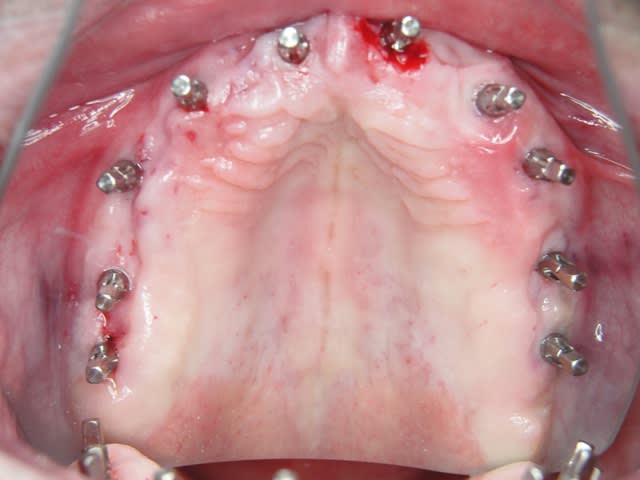

Un cas qui va sans doute prêter à discussions, juste pour montrer que la technique MIMI (non invasive) peut donner des résultats de qualité et esthétiques en moins de temps qu une chirurgie dite traditionnelle.

Les deux premières photos montrent le cas d´une jeune femme ( qui malheureusement s est fait retiré toutes les dents à l´étranger....).Ce cas a pu être terminé deux semaines après l´implantation.

Pour compléter le cas du dr Nedjat, dont j'utilise depuis plus de trois ans techniques et implants voilà un traitement d'édentement complet (en cours) avec des monoblocs aux axes corrigés par des prep caps en titane ou zircone qui sont cémentés. La prothèse complète du patient a été transformée en provisoire de qualité car au programme mois prochain il y a le bas..Toutes les photos et radios ont été faites jour de la pose. sauf la pano avant les ext bien sur :)

Ce weekend e je posterai une description détaillée de la technique sans lambeau MIMI avec des cas bien plus pointus que celui ci..a suivre